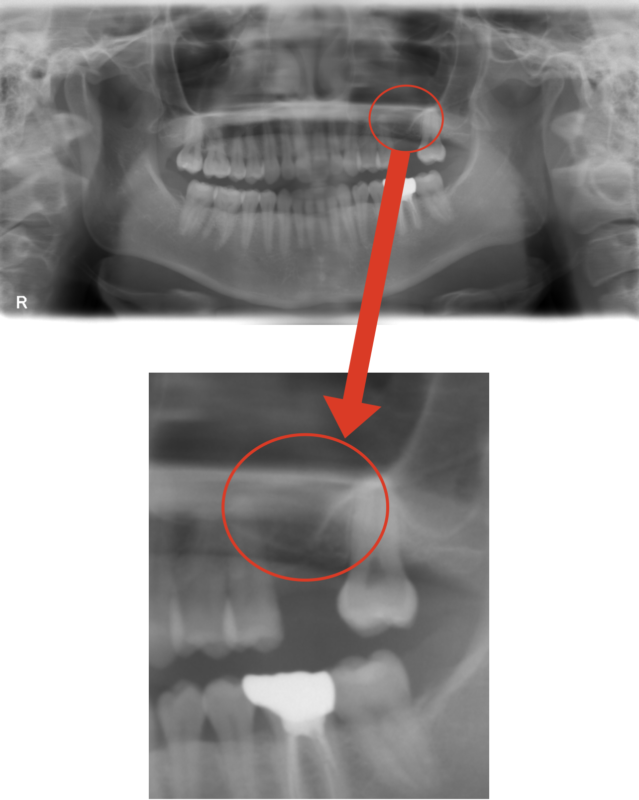

治療前写真

左上の6番目の歯が欠損した状態で来院されました。

レントゲンを見ると骨がかなり減っているのがわかります。

6番目の歯は必ず欲しい部位なのでインプラントをしたいところですが、

このままではインプラントも難しいため、ソケットリフトによる骨造成を提案しました。